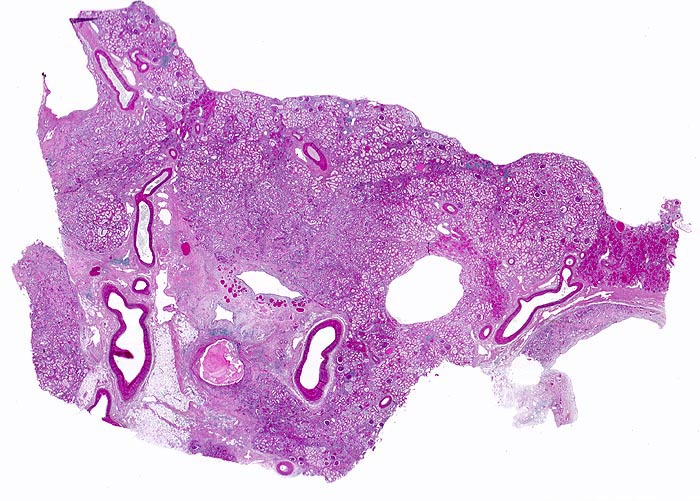

chronische Pyelonephritis

Niere

Die Nierenoberfläche ist grobhöckrig deformiert aufgrund muldenförmiger narbiger Einziehungen und zwischen den Narbenbezirken vorgewölbten erhaltenen Parenchymabschnitten. Infolge reaktiver Gefässwandverdickung erscheinen die Gefässe auffallend prominent. Im angeschnitten Nierenbecken: "scholliges Harnmukoid".

Makroskopisch ist die Nierenoberfläche grobhöckrig deformiert durch zahlreiche Narben mit teils rotem, teils weissem Grund. Beide Nieren sind verkleinert (Gewicht beider Nieren zusammen 180g). Das leicht ausgeweitete und gerötete Nierenbecken enthält mehrere kleine harte zackig begrenzte grauschwarze Kalziumoxalatsteine.

Nephrolithiasis und wiederholte akute pyelonephritische Schübe beidseits. Arterielle Hypertonie.